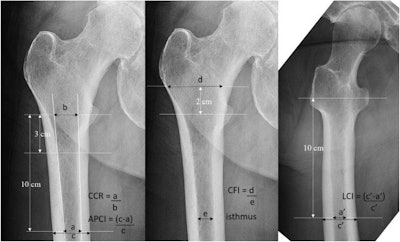

In this study, Lane and colleagues culled FRAX scores from 250 patients over the age of 50 who had hip replacements and 40 patients who had periprosthetic fractures. They then analyzed x-ray bone measurements -- namely, antero-posterior cortical thickness index (APCI) -- on preoperative x-rays from the patients. Finally, they analyzed correlations between the FRAX scores, the bone x-ray measurements, and periprosthetic fractures.

According to the findings, higher FRAX scores were significantly associated with lower cortical thickness. Importantly, patients who had periprosthetic fractures after hip replacements had significantly higher FRAX scores (19.61 vs. 15.15 for FRAX major; 8.53 vs. 5.39 for FRAX hip) and significantly lower antero-posterior cortical thicknesses (0.52 vs. 0.55), the researchers stated.